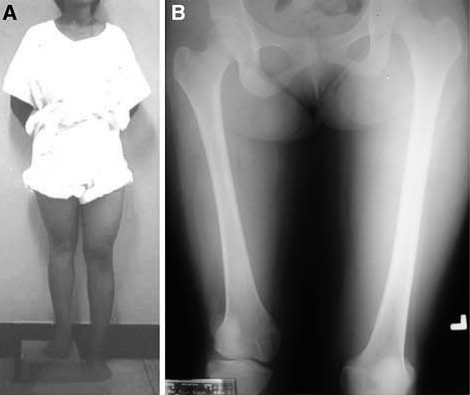

伊利扎洛夫骨延长技术。A.伊利扎洛夫骨延长法;B.在短缩骨干的上部做截骨;C.术后2周后,每天以1 mm距离牵拉延长截骨远端。

伊利扎洛夫的骨延长技术可以说实现了骨科「四维矫形」的完美理念,即三维外固定+时间变量(每天1 mm牵拉)。